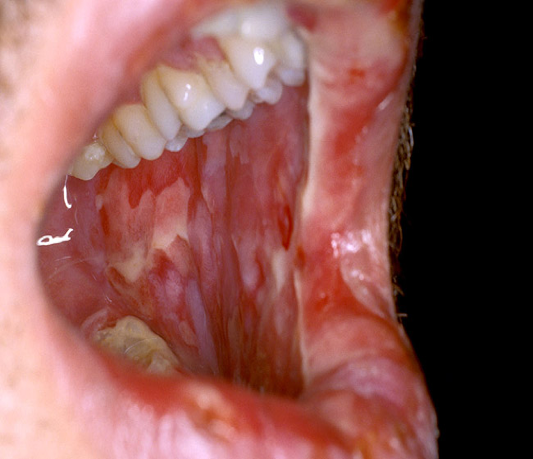

Profound inflammatory process of the mucous membranes and is characterized by:

- Initiation of insult (chemo)

- Upregulation/Generation of messenger signals and proinflammatory cytokines

- Signaling and Amplification

- Damage of tissue by cytokines is amplified via feedback loops

- Ulceration and inflammation

- Healing

Symptoms generally start to begin after day 7 and can range from mild inflammation to complete ulceration and inability to take anything PO. Epithelial sloughing after ulceration can produce the classic pseudomembane appearance. This desquamation can now lead to bacterial translocation in an already immunocompromised host.